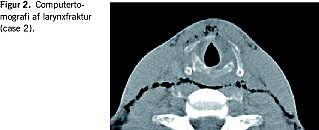

Case 3

29-årig mand henvistes fra egen læge på mistanke om larynxtraume. Patienten havde to dage tidligere været udsat for et enhånds kværkegreb og havde efterfølgende både hæshed, ændret stemme og smerter svarende til larynxskelettet. CT af halsen viste en fraktur af venstre cartilago thyroidea samt en kompensatorisk distortion af aryregionen (Figur 2 ). Rekonstruktion ved operation blev udført med absorberbar sutur hen over et stabiliserende titaniumnet igennem små borehuller i cartilago thyroidea, og man opnåede både symmetri og stabilitet af larynxskelettet. Ved postoperativ followup efter én uge, tre måneder og seks måneder havde patienten normal stemme ved stemmeanalysen og fuldstændig symmetriske forhold i endolarynx verificeret ved vidoeostroboskopi. Patienten havde dog nogle gener fra det implanterede titaniumnet ved hoveddrejning.